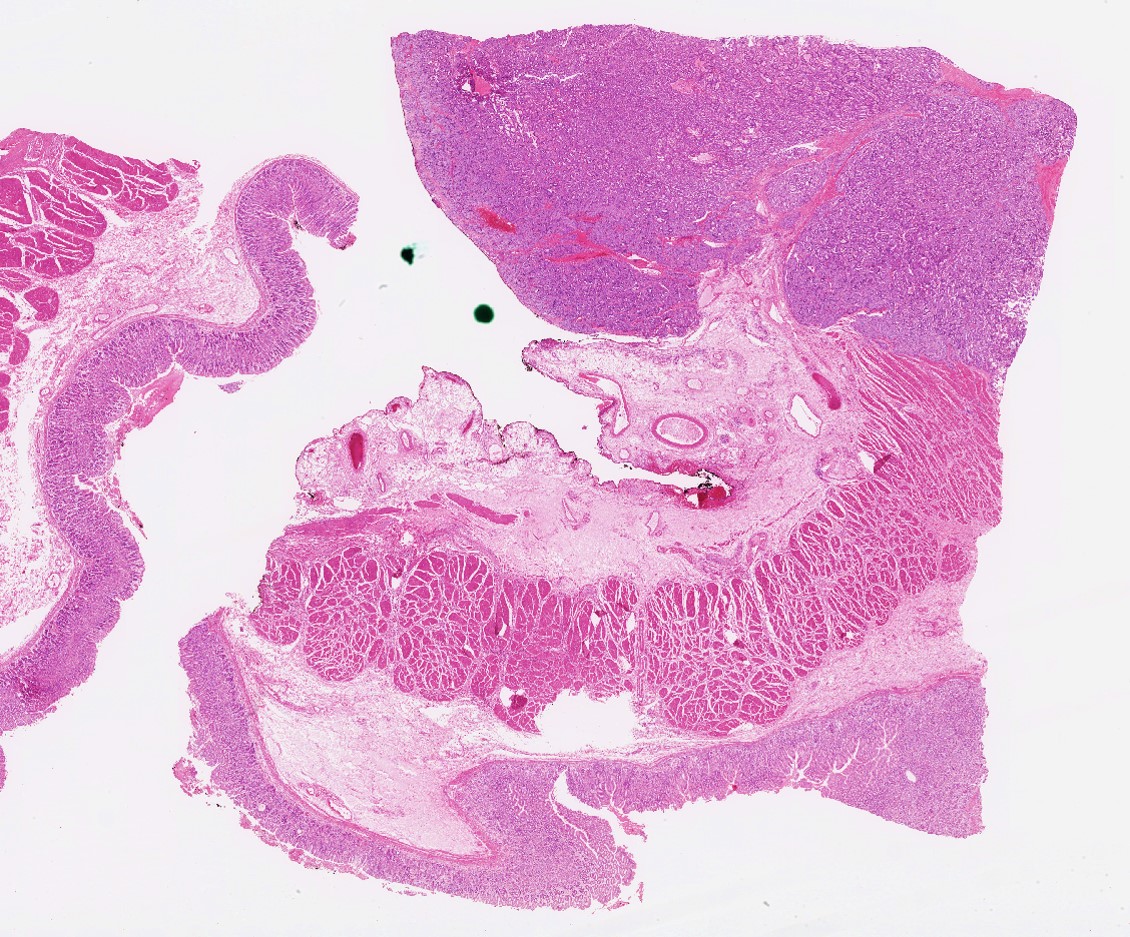

Gastroblastoma is a GLI1 (or EWSR1) translocation tumor that one reads in textbooks but may never encounter in practice. Surely I haven't seen another one since I graduated. #surgpath #pathX #pathtwitter #pathology #pathologists #stomach #cancer #GIpath